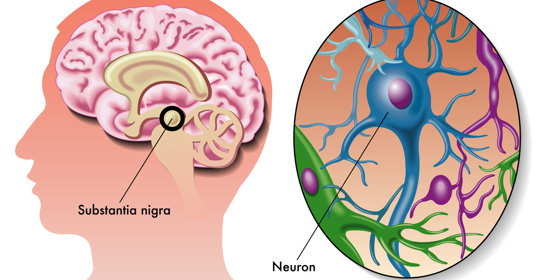

大腦與神經